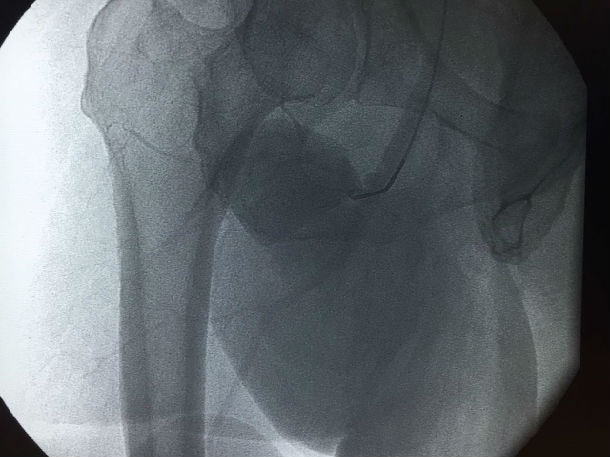

入院后查体:患者右腹股沟下1cm处可见一搏动性包块,6*9cm,边界清楚,质偏软,表面无红肿及淤血,表面皮肤完整,无破溃。

超声提示:右侧腹股沟区见假性动脉瘤形成伴附壁血栓形成,囊性包块6.5*10.3cm,与髂外动脉相同,可见红蓝相间的血流信号。

春节将至,能否给患者和医务人员的我们一个满意的答卷呢?周全的手术方案和万全的准备是必须的。看似简单的股深动脉瘤,确实是对我们技术的严峻挑战。分析病例我们不难发现该病例的一些特点:如果我们采用传统的外科手术方式是较为安全的,但是其中潜在的问题,如开刀风险、手术创面大,术后淋巴管漏等并发症较多,另外术后恢复时间较长,在这特殊时间内对患者来说并不是最好的选择。有没有更简单、经济、创伤较小的方法呢?经讨论后提出多种手术方案:最理想治疗是用小型覆膜支架封堵瘤体口,但是,根据患者下肢血管CTA提示,该患者髂动脉严重迂曲,成角偏小,右侧髂动脉迂曲成直角,入路困难,另覆膜支架顺应性差,植入困难,费用也较大,作为备选方案。如果用传统单纯的弹簧圈治疗,巨大假腔,费用大,疗效不确切,并且有可能会有远期不适,也列入备选方案。还有就是经左侧穿刺,翻山至右侧股深动脉,小球囊封闭瘤体口,经球囊向瘤体内注射凝血酶,待自身形成血栓后,释放球囊,用2枚裸支架覆盖瘤体口,这样既减少创伤,减少费用,同时可防止瘤体内血栓脱落至股深动脉,此手术方案较为理想。那么实际操作中会是怎样的结果,我们无法预知,充足的术前准备显得尤为重要。入路的选择:患者高度肥胖,股动脉穿刺困难(脂肪厚股动脉触摸困难,穿刺要求很高,一旦出问题后果不堪设想)。支架的选择,我们联系多方厂家备用所有可能会用到的支架,介入治疗失败或是操作受限后外科的手术也全部就位。2016-02-03手术在计划中进行,患者体型肥胖,股动脉触摸困难,穿刺就是一个挑战,凭我们丰富的经验,一针见血,穿刺成功通过,更严峻的挑战还在后面,置管造影显示,患者髂动脉严重迂曲,多处迂曲近直角,所有的操作都需谨慎小心,防止导管打折、断裂,引起出血,另多次在各个分支和假腔血管间选择,假腔内操作容易导致瘤体破裂,造成大出血,技术难度大。手术紧张而有序,反复确认瘤体开口口径及有无流出道后,球囊顺利送达瘤体口内,经球囊注射凝血酶,能否形成血栓,大家拭目以待。20min过去了,透视见瘤体内预先残留的造影剂不再消失,自身血栓形成,看到了成功的希望,由于患者动脉迂曲严重,翻山鞘管规格有限,覆膜支架顺应性差,鞘管支撑力不够,经各位医生讨论后,决定用2枚裸支架代替,精确定位后,顺利释放支架,复造影见支架位置良好,贴壁良好,无明显血流渗入瘤体,瘤体搏动消失。患者目前恢复良好,预计可以在春节前2天回家过年。